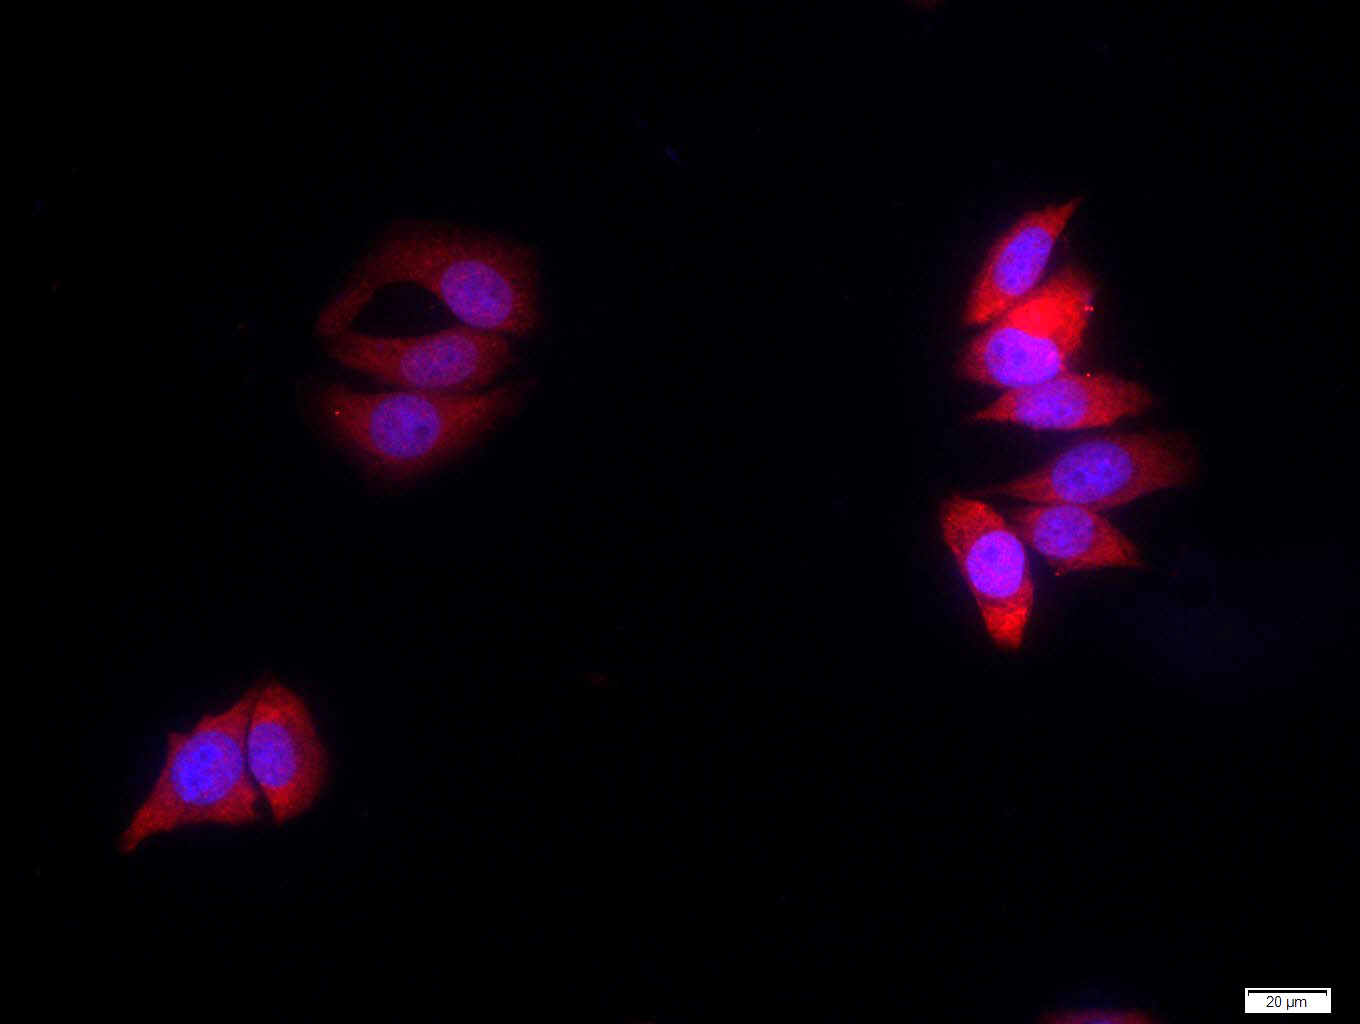

Tissue/cell: MCF7 cell; 4% Paraformaldehyde-fixed; Triton X-100 at room temperature for 20 min; Blocking buffer (normal goat serum, C-0005) at 37°C for 20 min; Antibody incubation with (Amyloid Precursor Protein) polyclonal Antibody, Unconjugated (bs-0112R) 1:100, 90 minutes at 37°C; followed by a FITC conjugated Goat Anti-Rabbit IgG antibody at 37°C for 90 minutes, DAPI (blue, C02-04002) was used to stain the cell nuclei.